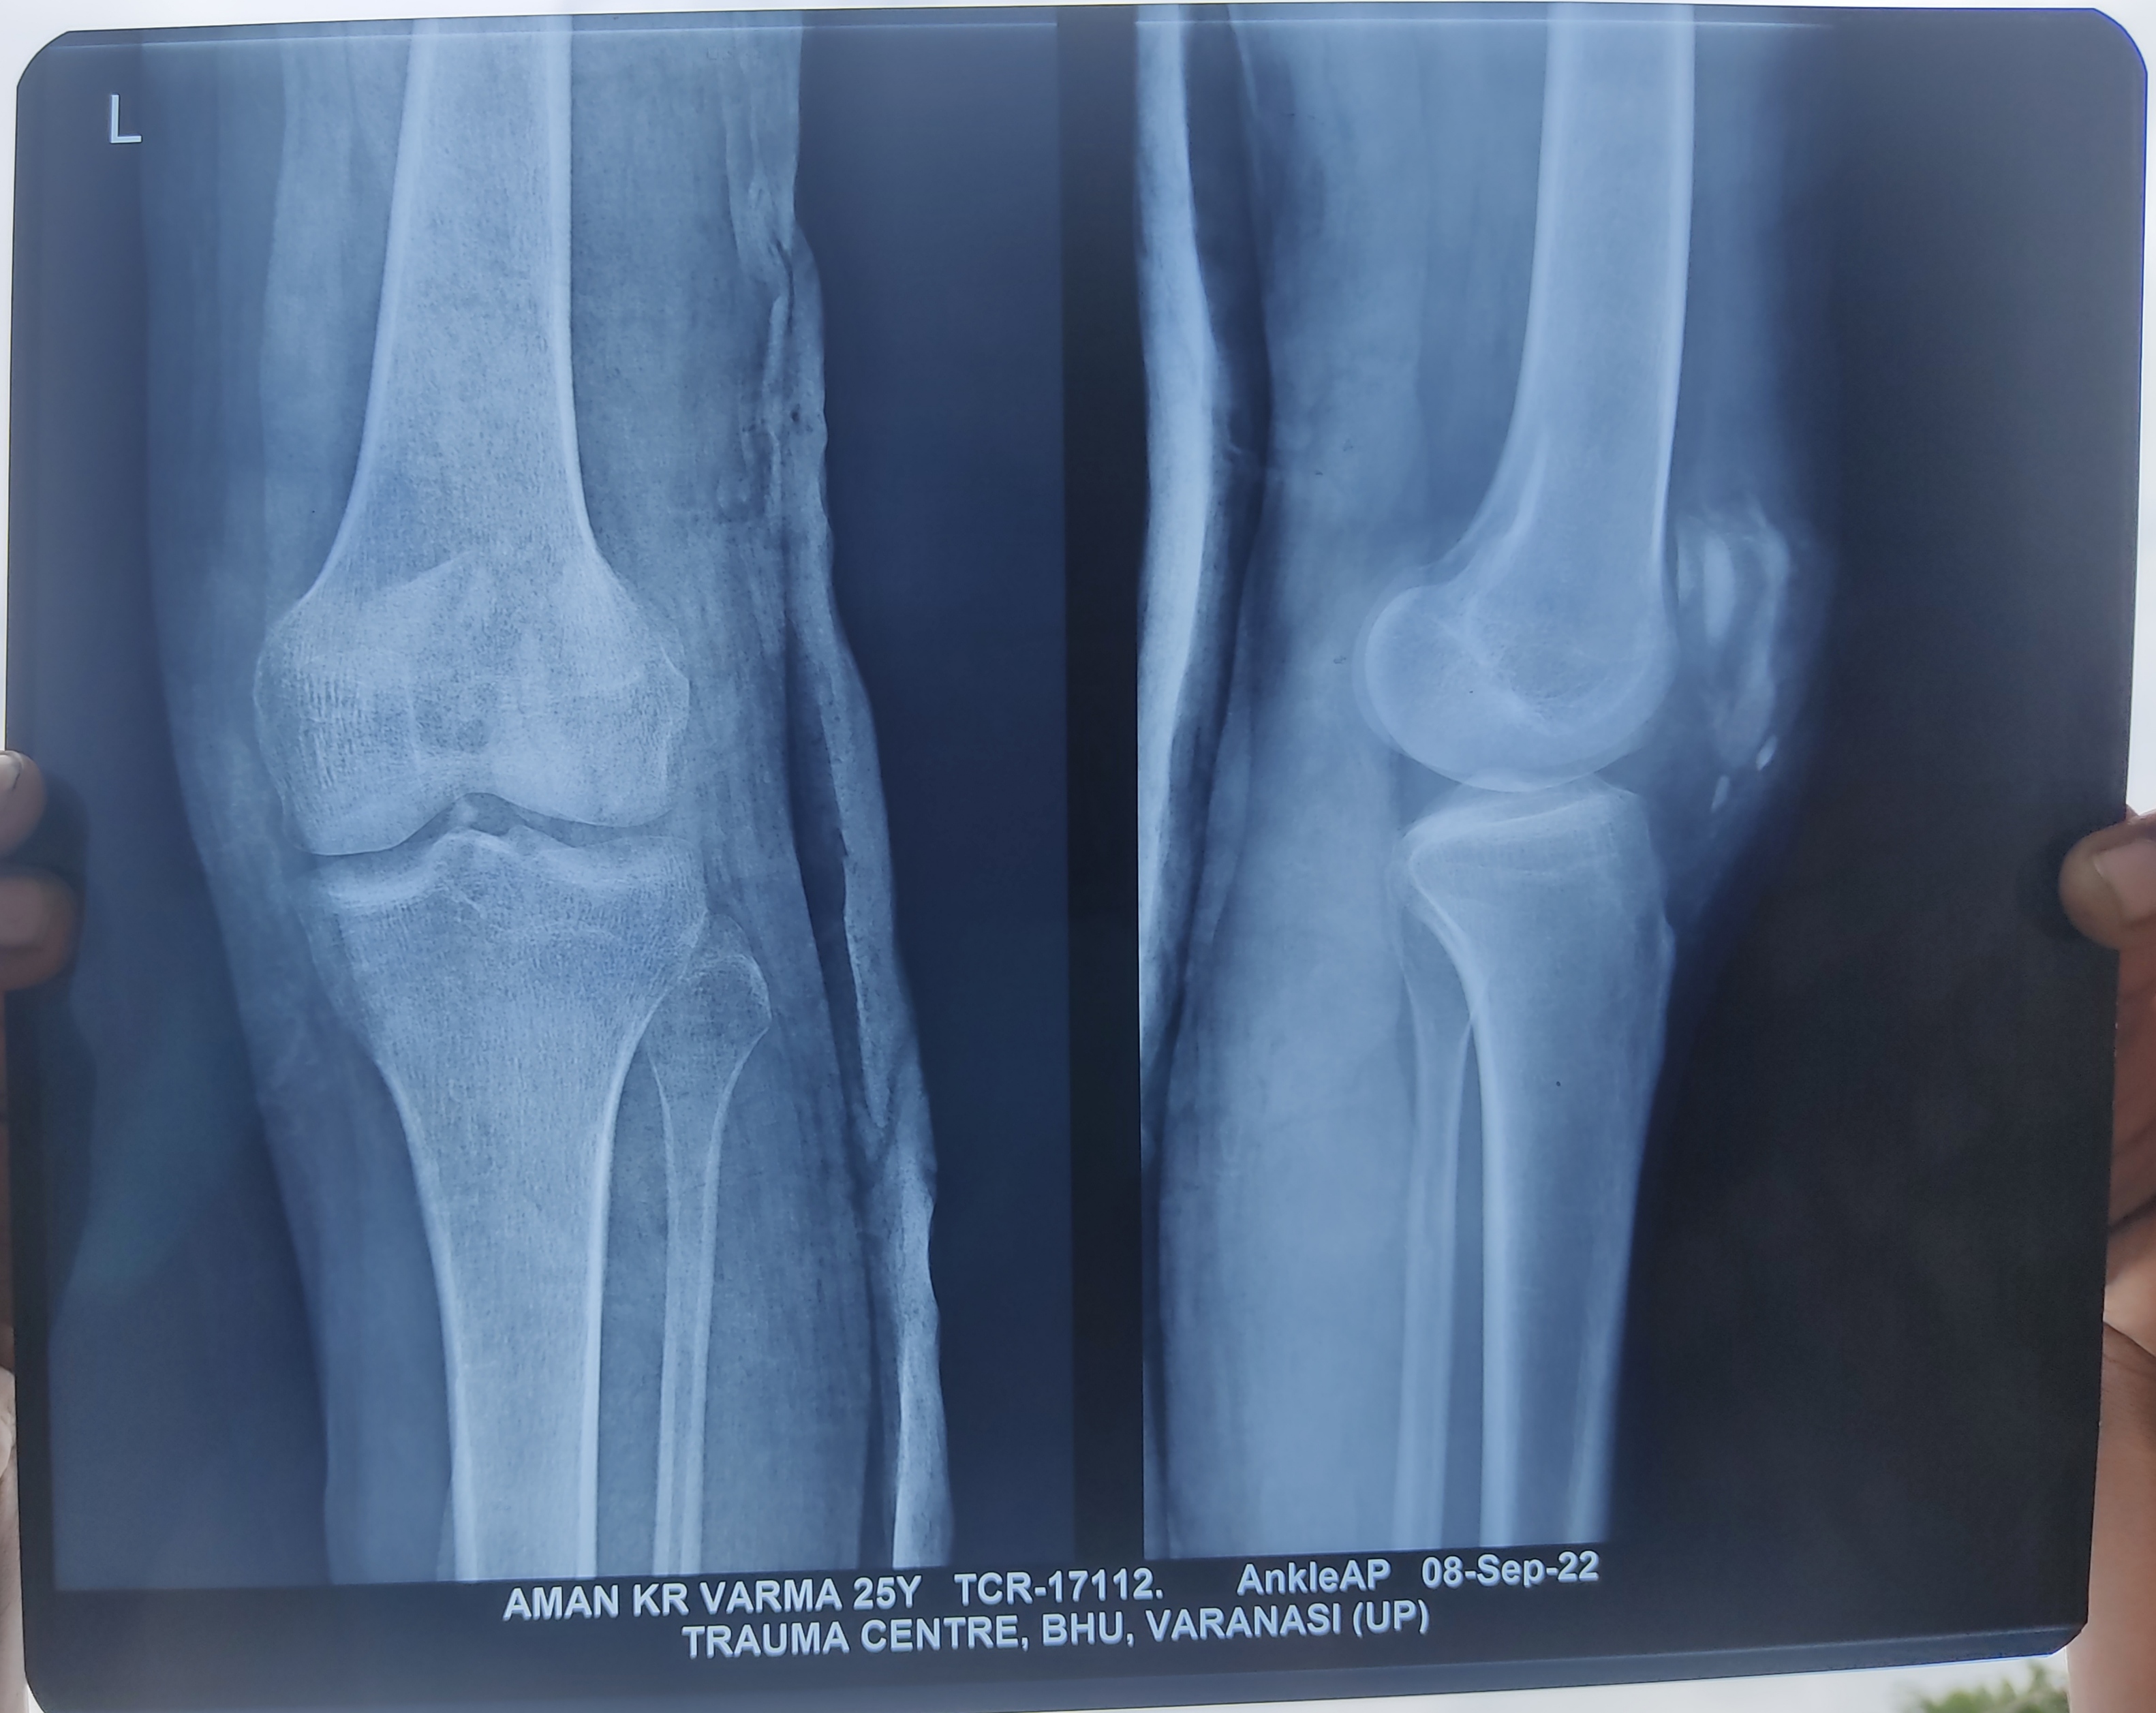

Sir mera MRI nhi hua h aur chal nhi pata jra bhi mai chot ka foto bhi bhej rha hu

Vedio , aur pdf k sath xray bheja hu whatsup no pr thod dhyan de dijiye please

Hello sir aap x ray bhi mange the mai aapko xray de rha hu dekhiye MRI bhi bhej diya hu aapko aapke no pr bhi bheja hu sir bataiye please

Hello sir aaj 8 hapte jo gye h koi surgery ya opration nhi hua h accident k bat bs tanke  lge the mera pair 10 digree mud rha h keval bhut koshi kr rha hun nhi improve ho rha h MRI  doctor dekh kr bol rhe h ki plate lgana  padega pair munde lgega please sir aap bataiye MRI dekh kr ki kya mera pair mud jayega ki nhi abhi 8 hapte hi huye h

Please bhut preshan hu mai

सर मेरा accident 25 अगस्त को हुआ था BHU TRAUMA CENTER (VARANASI) मे हो रहा है 9 टाके लगे थे मेरे घुटने पर 1 महीना 10 दिन हो गया लेकिन मेरा पैर मुड़ नहीं रहा है अभी आपरेशन भी नहीं हुआ हैं डॉक्टर भी सही गाइड नहीं कर रहे है मुझको मैं खड़ा नहीं हो पा रहा , खड़ा होता हूँ तो पैर कांपने लगता है यहाँँ पर मुझको कोई उम्मीद नहीं दिख रही है exercises भी कर रहा कुछ नहीं हो रहा 10 डिग्री मुड़ रहा हैं केवल आप ही मेरी आखिरी उम्मीद है सर please mera pair mod dijiye please??